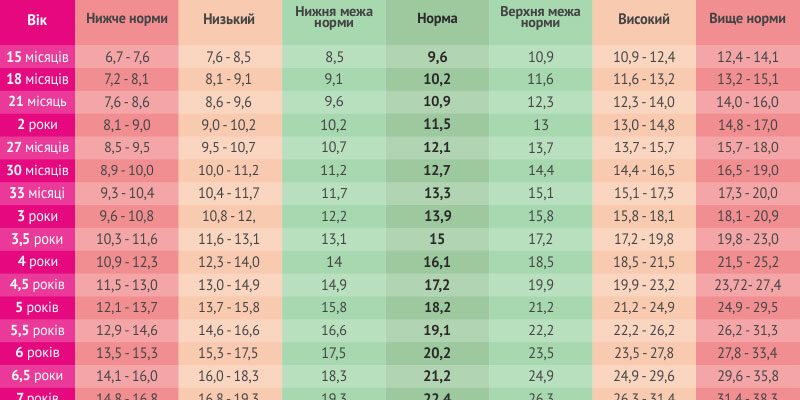

Зріст дитини 10 років: на що звернути увагу Якщо вас цікавить зріст дитини 10 років, ви не самотні. Багато батьків часто задумуються про те, наскільки